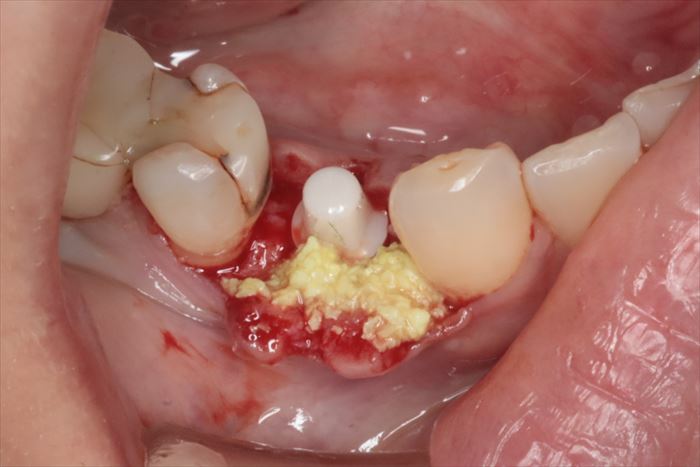

埋入後に頬側骨の裂開は見られませんでしたが、矢印の陥凹部分に骨移植材を填入して

骨増生処置(GBR)を行います。

歯肉弁を封筒状に粘膜剥離し、骨移植材と抗生物質を混和したものを準備します。

_

骨の陥凹部分に骨移植材を填入して膨らみが出ました。

骨となって治癒していきます。

今後の骨吸収を防ぐための予防的な骨増生処置という概念です。